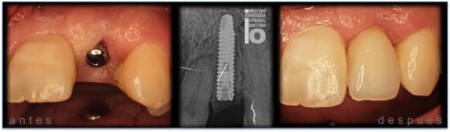

IMPLANTE EN INCISIVO LATERAL SUPERIOR POR AGENESIA

IMPLANTE EN INCISIVO CENTRAL SUPERIOR.